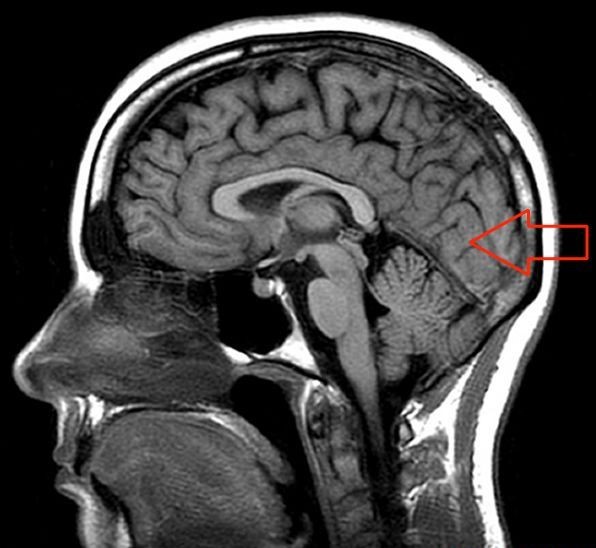

13. Name the arrowed structure